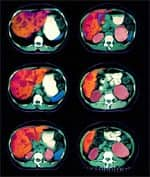

Recent studies suggest that some Asians—who demonstrate genetic polymorphisms, or variability in the genes that code for the enzymes alcohol dehydrogenase and aldehyde dehydrogenase—are at elevated risk of developing alcohol- related liver disease, as are African-Americans of either sex.38,39 In fact, African-Americans have been dying of liver cirrhosis at a greater rate than whites of comparable age for the last 40 years.40 However, neither men nor women enjoy any relative advantages when it comes to protecting against the toxic effects of the powerful 1-hydroxy-ethyl radical. Because alcohol has substantial caloric value (7.1 calories per gram), it may displace ordinary nutrients in the diet, including antioxidants such as vitamin C, thereby causing primary malnutrition.23 Secondary malnutrition can occur later in the course of chronic alcohol use, when food is no longer properly digested and absorbed by the gastrointestinal tract.30,41-43 Long-term alcohol abuse often leads to a condition known as cirrhosis, which is responsible for the high rate of mortality among heavy drinkers. While liver disease was long thought to be caused by malnutrition, scientists eventually demonstrated that alcohol causes liver cirrhosis even in the absence of nutritional deficiencies. Liver cirrhosis was the twelfth leading cause of death in the US in 2000.35,44 The correlation between alcohol intake and cirrhosis is confirmed in epidemiological data gathered in the last century. For example, Canadian scientists recently analyzed alcohol consumption and cirrhosis incidence in the US before, during, and after Prohibition. The data provide striking evidence of the close correlation between drinking and incidence of the disease. As alcohol consumption plummeted during the Prohibition era, cirrhosis closely followed suit. With the repeal of Prohibition, drinking resumed with gusto, as did diagnoses of fatal liver cirrhosis. The nefarious cause-and-effect relationship between alcohol consumption and deadly cirrhosis continues to this day.35 | ||||||